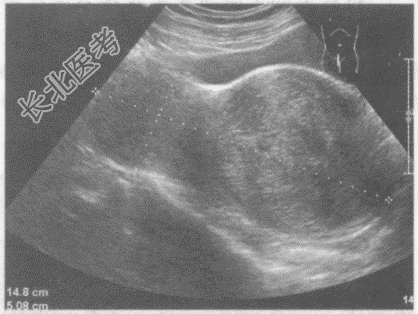

- 单项选择题临床资料:女性患者, 42岁,自述下腹坠胀, 月经量增多3年余。

超声综合描述:子宫前位, 宫颈部可见7.8cm×7.2cm低回声区,边界清晰, 形态规则,内回声不均匀, 呈漩涡状,向外突起, CDFI:周边可见少许血管绕行, 呈动脉血流频谱。见下图及彩图105。

超声提示: A、阔韧带肌瘤

B、子宫颈肌瘤

C、子宫颈妊娠

D、子宫颈癌

E、子宫腺肌病